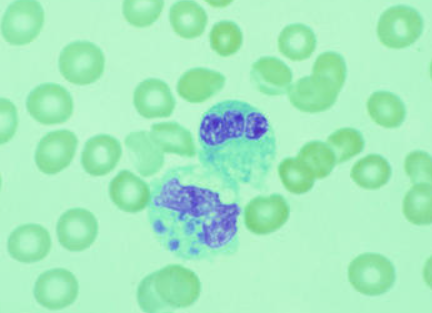

查菲埃立克体在光学显微镜下主要以包涵体的形式存在于宿主细胞胞质内的空泡中,形似桑甚,也称为桑葚体,用吉姆萨染色,可见查菲埃立克体包涵体被染成紫色(图2)。而电子显微镜下,存在球形及球杆形2种形态。球形体是中心电子密度增高的类核DNA和核糖体,又叫实体,大小为(0.4-0.6) μm;球杆形体核糖体及类核DNA纤维均匀一致地分布于整个细胞质,又叫网状体,大小为(0.4-0.6) μm×(0.7-1.9) μm。这两种类型的细胞均以二分裂方式繁殖,均具有革兰氏阴性菌细胞壁,含有极丰富的肽聚糖[1]。

图2 查菲埃立克体光学显微镜下照片[1]

(1)传统方法:去可以样本进行涂片后进行吉姆萨染色,在光学显微镜下观察,可见单核细胞的胞质内有呈圆形的包涵体,并且该包涵体被染成紫色。